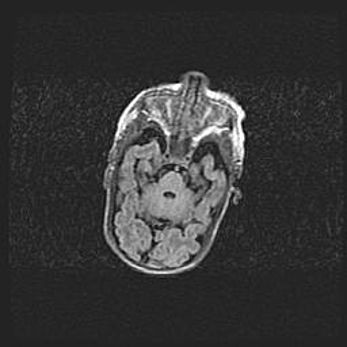

Лейкомаляция с кистозно-глиозной дегенерацией головного мозга.

Возраст: 2 месяца 25 дней

Вес: 6400 г

Окружность головы: 40 см

Срок гестации: 41 неделя

Лейкомаляцию относят к ишемически-гипоксическим повреждениям головного мозга, диагностируемым у новорожденных. При лейкомаляции в головном мозге обнаруживают очаги некроза, возникшие после тяжелой гипоксии и нарушения кровотока. В процессе морфогенеза очаги проходят три стадии: 1) развития некроза, 2) резорбции и 3) формирования глиозного рубца или кисты. Перивентрикулярная лейкомаляция (ПЛ) встречается примерно в 12% случаев среди новорожденных, обычно – у недоношенных детей, причем, частота ее зависит от массы, с которой младенец появился на свет. Наибольшее число малышей страдает лейкомаляцией, если масса при рождении 1500-2500 г.